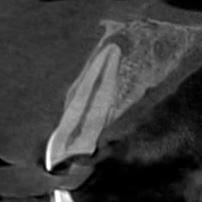

3D цефалометричний аналіз є сучасною технологією, яка дозволяє отримувати точніші,

комплексніші та надійніші дані про зубну та скелетну структуру. Ця технологія може стати

великим кроком в перед для ортодонтів, які хочуть забезпечити найкраще можливе лікування

своїх пацієнтів.

Основні переваги 3D цефалометричного аналізу:

Точність: 3D цефалометричний аналіз забезпечує точніше визначення розмірів та відстаней між

зубами та кістковими структурами.

Комплексність: ця технологія дозволяє отримувати детальні дані про різні структури, такі як

кістка та м'язи, що дозволяє ортодонтам докладніше досліджувати деякі патології та планувати

лікування.

Надійність: 3D цефалометричний аналіз дозволяє отримувати надійніші результати, оскільки

виключає можливість помилок, пов'язаних зі спотворенням або перекриттям зображень.

Оскільки 3D цефалометричний аналіз - це досить нова технологія, вона все ще не доступна в

усіх клініках та ортодонтічних практиках. Крім того, вона може вимагати додаткової

підготовки та спеціалізованого обладнання. Однак, завдяки своїм перевагам, вона стає все

більш популярною та знаходить застосування в ортодонтичній практиці.